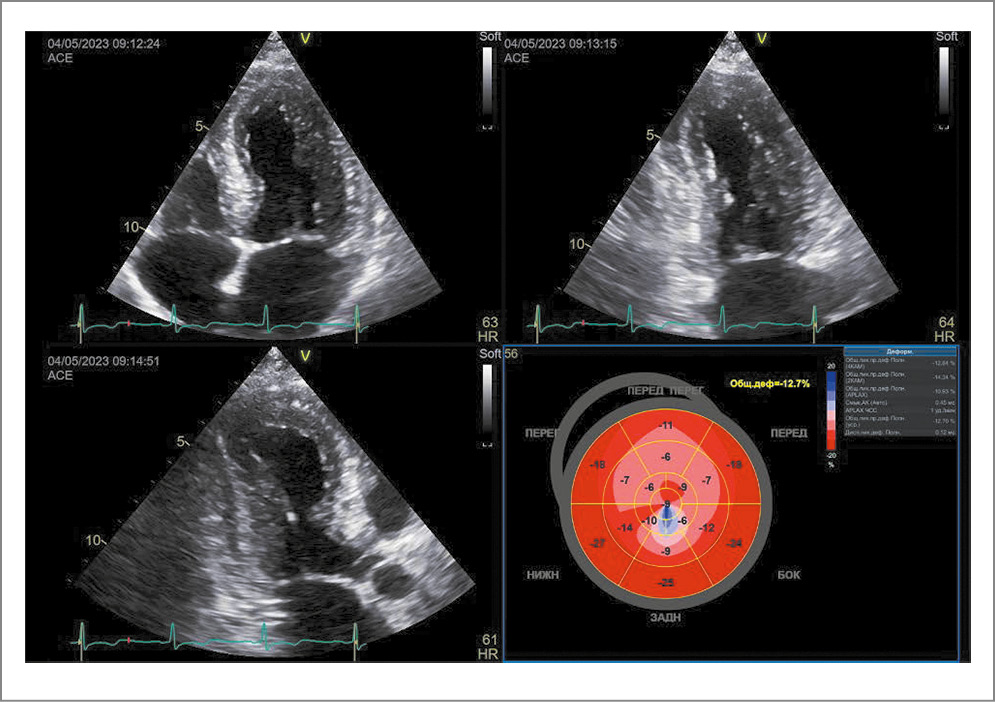

По данным ЭхоКГ – положительная динамика в виде увеличения ФВ ЛЖ до 59% (по Simpson). Сохранился гипокинез апикальных сегментов передне-перегородочной стенки и межжелудочковой перегородки, в остальных сегментах отмечался нормокинез. Регистрировалась положительная динамика показателя GLS: уменьшение с -11,2% до -14,5%, при норме менее -15% (рис. 8).

Рис. 8. Эхокардиограмма на 10-е сутки госпитализации.